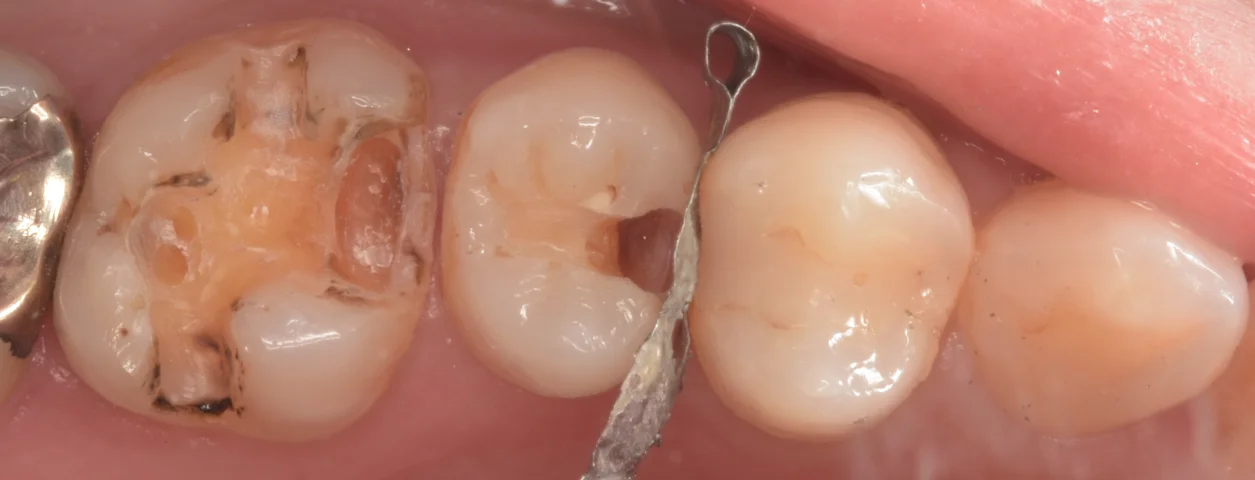

まずは術前からです。

画像の左2本の治療を行いました。

さて、虫歯を見やすくしたのがこちらです。

基本的に歯と歯の間を削る時に隣の歯を傷つけてしまうと、そこから隣の歯が虫歯になってしまうリスクが上がっていくので、私はこのように金属の壁を入れて保護しながらやって行ってることが多いです。

どちらも右側の歯との間が大きく虫歯になっています。

左側の歯についてはそのまた左の歯との間から虫歯が入り込んできてそうなのがわかりますね。